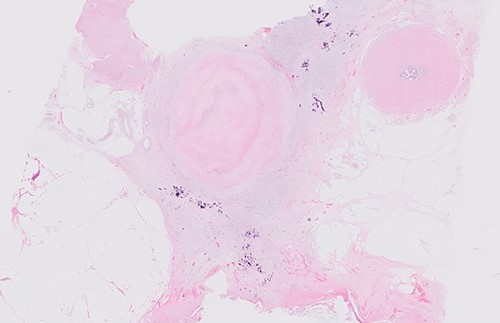

Postoperative histology demonstrated complete pathological response and an R0 resection (ypT0 N0(0/46) M0R0; Fig. 3). The patient proceeded to completion chemotherapy of 6 cycles of FOLFOX (folinic acid, fluorouracil and oxiliplatin) at 6 weeks postoperatively. He was then entered into a formal surveillance programme.

DISCUSSION